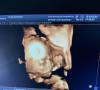

Такая вероятность тоже есть. Скрининг когда делали лицо прятала 🙈. Пришлось гулять и есть шоколад. А нужно было обязательно личико посмотреть (нос и нижнюю челюсть). Тк до этого риски были, хотя ХА исключили по анализам еще до второго скрининга

У вас мальчик или девочка? Как будто человека разбудили )